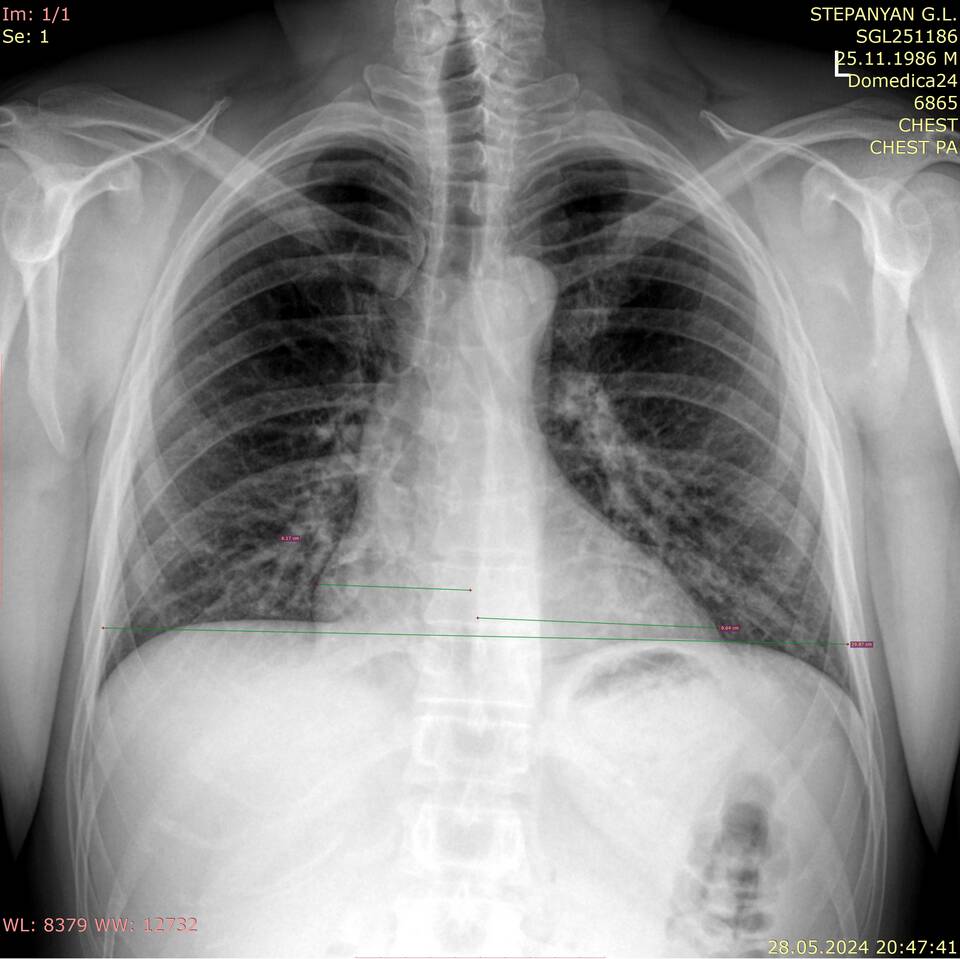

• Четкая визуализация результатов